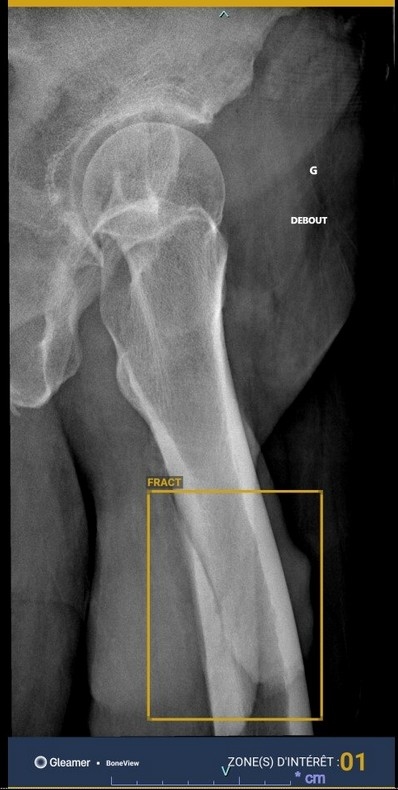

domingo chavez | Fini les médecins avec l'IA ?